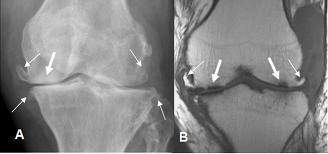

Ocasionalmente veremos a niños tratados previamente como artritis reumática y que nos lo derivan después de mucho tiempo de usar esteroides, que lo mejoraban temporalmente hasta que la leucemia se muestra progresiva, otras veces vienen niños que han sido tratados como asma con mejoría leve hasta que miramos su radiografía de tórax y nos damos con la sorpresa de una masa en mediastino que obliga a tomar análisis y ocasionalmente vendrá un paciente disminución de fuerzas de los miembros inferiores cuya TAC sugiere un tumor de la columna vertebral, es intervenido

y se diagnostica leucemia aguda que infiltra la vértebra, que mejora y se salva con el tratamiento oportuno. Estas presentaciones son ocasiónales y se debe a que en los niños todos los huesos tienen médula ósea que puede ser el asiento de las primeras manifestaciones de la enfermedad, al expandirse el hueso por la infiltración leucémica, dará artritis si se ubica en la rodilla o paraplejia si compromete la columna vertebral. En caso de comprometer ganglios linfáticos éstos crecerán donde se encuentren, en el caso de los ganglios mediastinales estos crecerán hasta dificultar la correcta función del proceso respiratorio .Si el diagnóstico se confirma el tratamiento quimioterápico aliviará la sintomatología, la Radioterapia en mediastino está indicada de no responder al tratamiento previo.